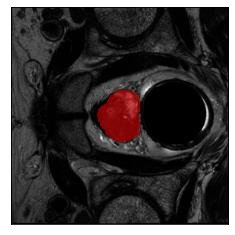

Machine learning models are typically deployed in a test setting that differs from the training setting, potentially leading to decreased model performance because of domain shift. If we could estimate the performance that a pre-trained model would achieve on data from a specific deployment setting, for example a certain clinic, we could judge whether the model could safely be deployed or if its performance degrades unacceptably on the specific data. Existing approaches estimate this based on the confidence of predictions made on unlabeled test data from the deployment's domain. We find existing methods struggle with data that present class imbalance, because the methods used to calibrate confidence do not account for bias induced by class imbalance, consequently failing to estimate class-wise accuracy. Here, we introduce class-wise calibration within the framework of performance estimation for imbalanced datasets. Specifically, we derive class-specific modifications of state-of-the-art confidence-based model evaluation methods including temperature scaling (TS), difference of confidences (DoC), and average thresholded confidence (ATC). We also extend the methods to estimate Dice similarity coefficient (DSC) in image segmentation. We conduct experiments on four tasks and find the proposed modifications consistently improve the estimation accuracy for imbalanced datasets. Our methods improve accuracy estimation by 18\% in classification under natural domain shifts, and double the estimation accuracy on segmentation tasks, when compared with prior methods.